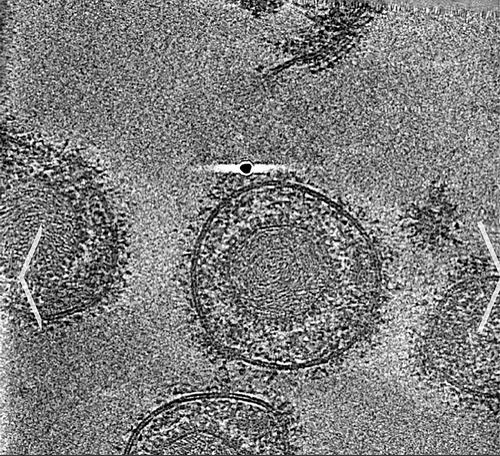

疱疹病毒颗粒冷冻电镜图像。

对抗疱疹的纳米抗体

全球每年新增疱疹病毒感染者超4000万人。该病毒对新生儿、免疫力低下人群威胁极大,可引发重症感染甚至死亡。疱疹病毒侵染宿主细胞的关键在于其包膜糖蛋白B(gB)介导的膜融合过程,gB通过构象变化推动病毒与宿主细胞膜融合,然后释放遗传物质完成增殖。gB是潜在药物靶点,但因其关键区域无法接近或受到保护,目前尚无靶向药物。

针对上述问题,马普多学科科学研究所等借助冷冻电镜解析出gB融合前激活状态的高分辨率结构,还从gB免疫羊驼体内筛选出一种微型纳米抗体。该抗体可在极低浓度下结合gB融合前构象,阻断其构象变化,从而抑制膜融合,并能同时中和1型和2型单纯疱疹病毒。这一发现为疱疹病毒感染防治开辟了新路径,为免疫力低下群体带来福音。